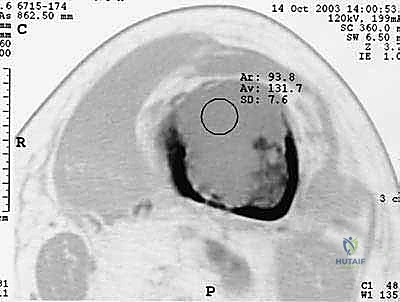

| التصوير المقطعي (CT Scan) | تقييم الهيكل العظمي بدقة ثلاثية الأبعاد. | دقة عالية جداً. أساسي للتخطيط الجراحي وقياس حجم التآكل العظمي. |

| الرنين المغناطيسي (MRI) | تقييم الأنسجة الرخوة، نخاع العظم، والحبل الشوكي. | ممتاز للكشف المبكر جداً ولتحديد مدى انضغاط الأعصاب الشوكية. |